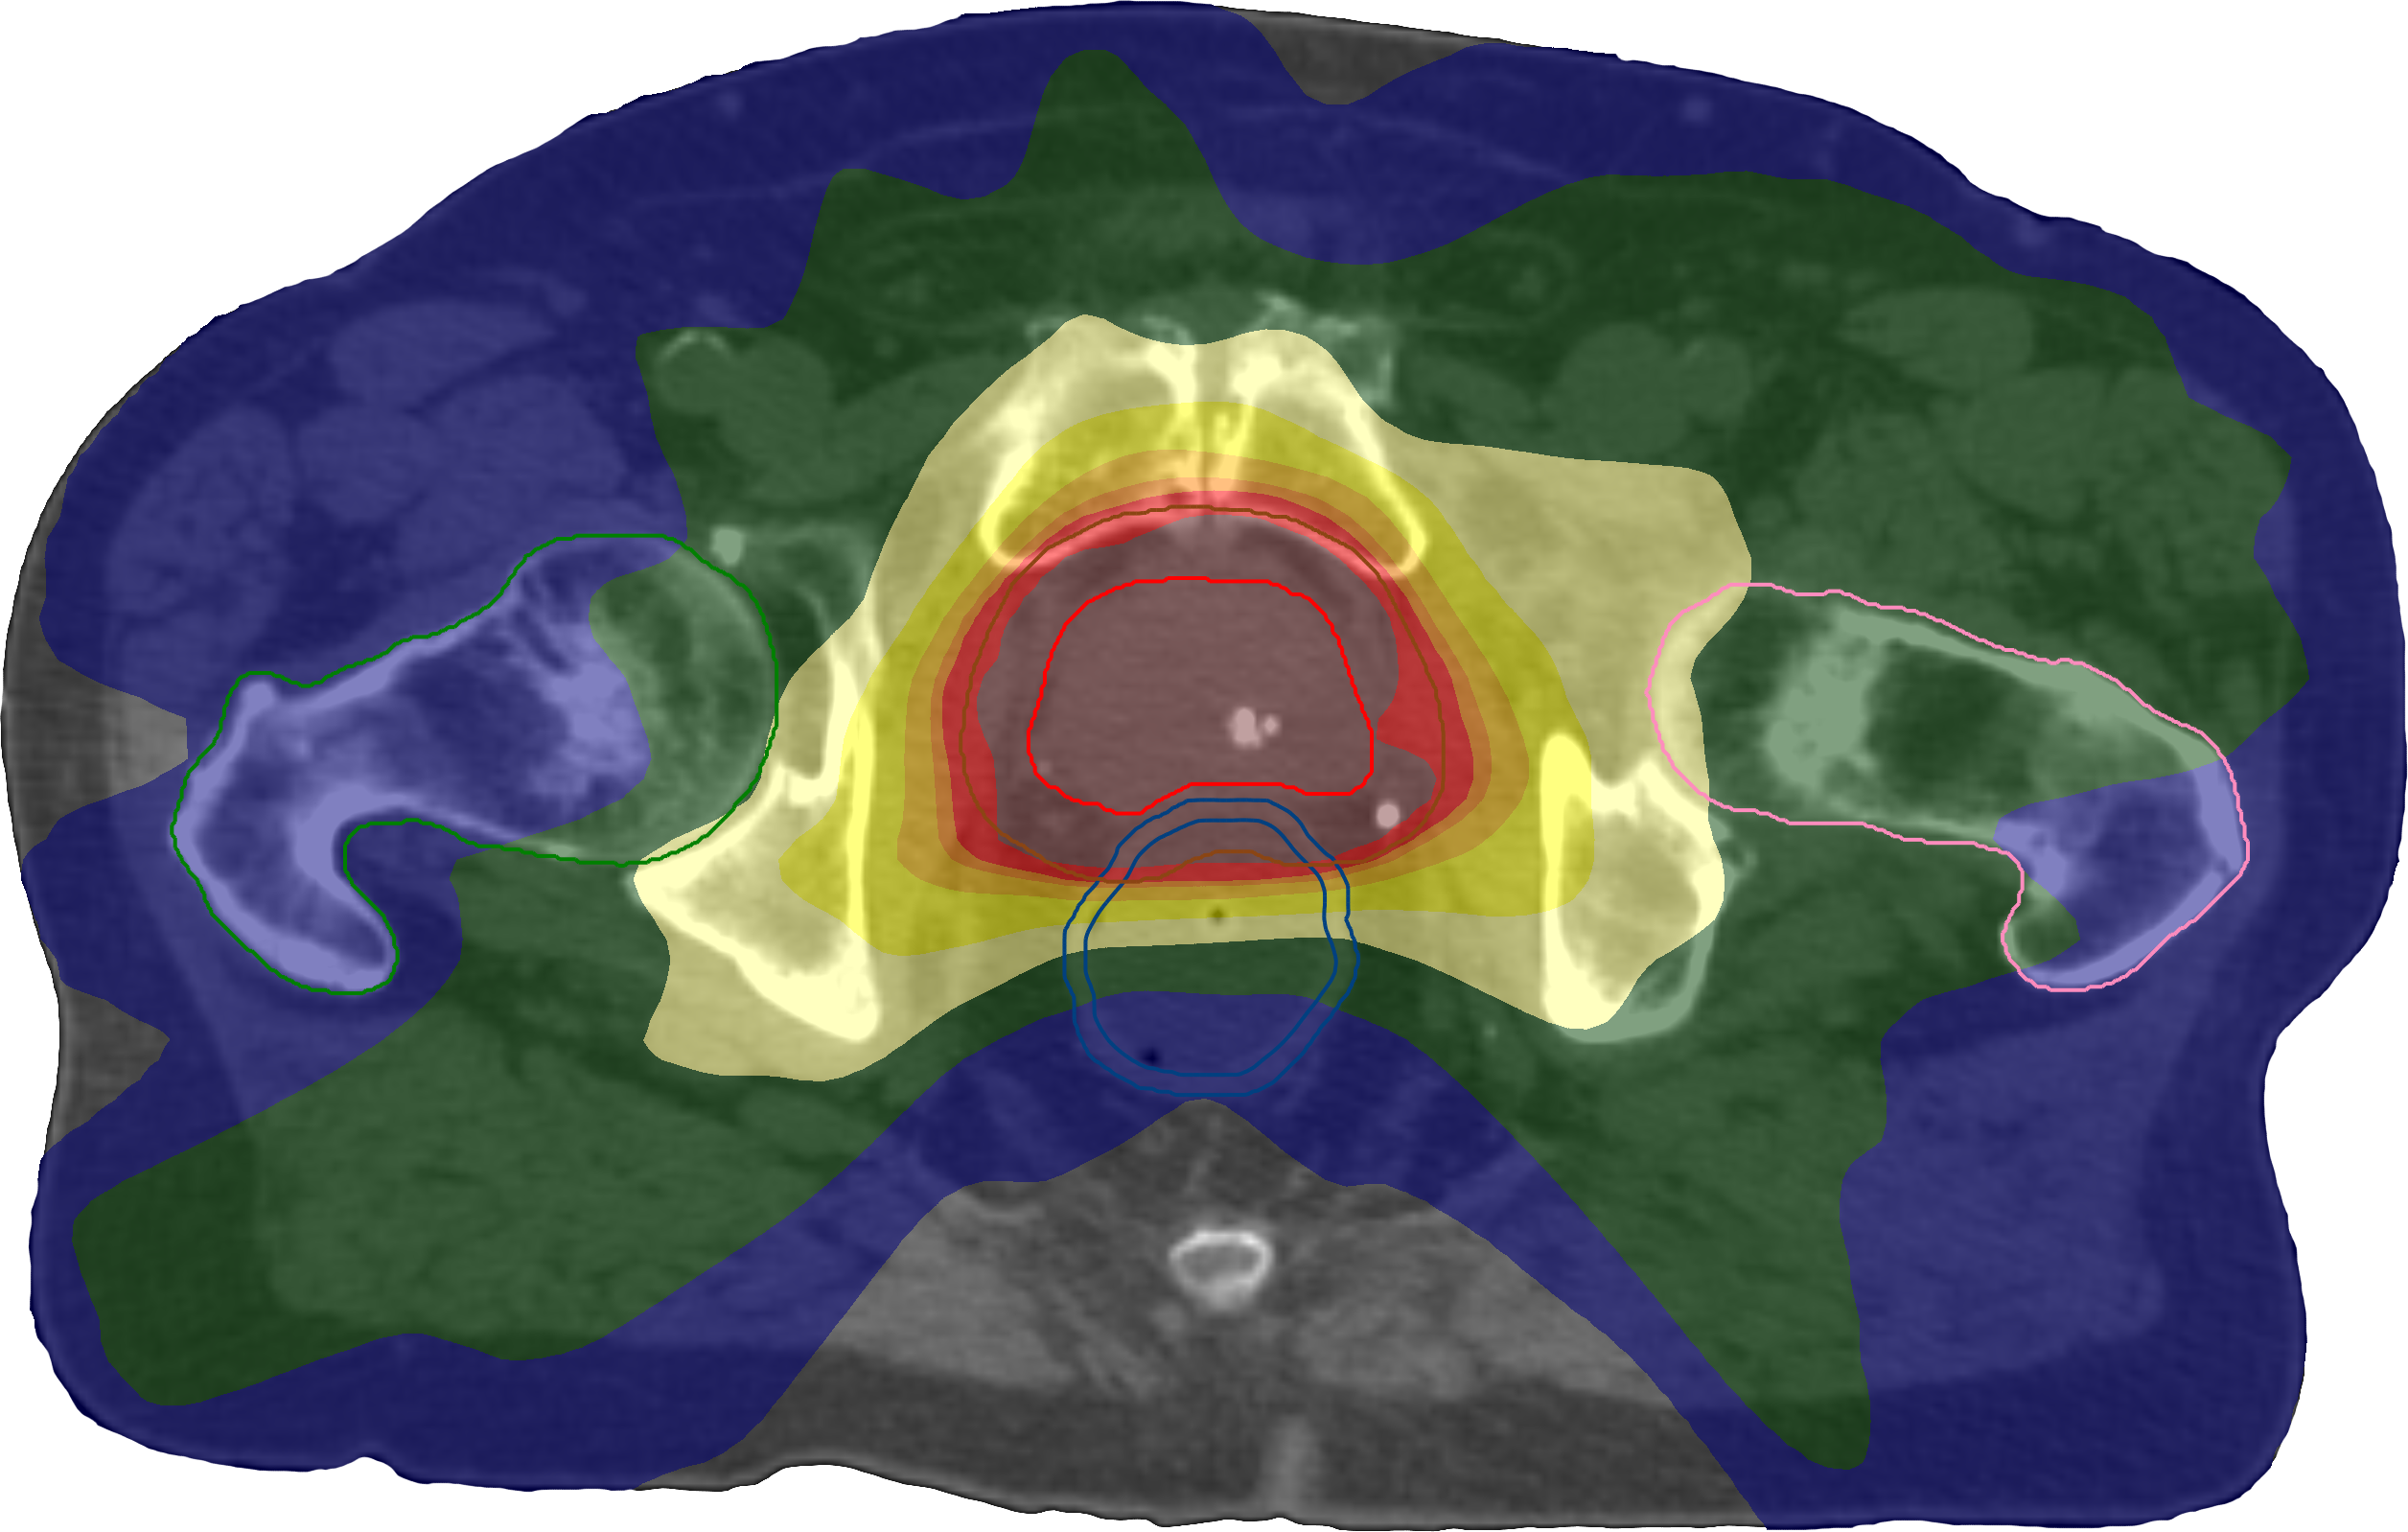

Figure 2 shows DVH comparisons between the formulations, and Figure 3 shows the spatial dose distributions. One can observe that the use of mean-tail-dose for the PTV tails leads to fewer extreme values in the lower tail, as can be expected from its properties—the D99.5%subscriptDpercent99.5\operatorname{D}_{99.5\,\%}D0.5%subscriptDpercent0.5\operatorname{D}_{0.5\,\%} range for the PTV was 5690cGy5690cGy5690\;\mathrm{cGy}6207cGy6207cGy6207\;\mathrm{cGy} for this case, compared to 5565cGy5565cGy5565\;\mathrm{cGy}6222cGy6222cGy6222\;\mathrm{cGy} for the case with only dose-at-volume and 5279cGy5279cGy5279\;\mathrm{cGy}6273cGy6273cGy6273\;\mathrm{cGy} for the conventional formulation. It is also possible to see the effect of the goals being made more restrictive when using the same reference volume level in the replacement. Moreover, the relatively large CI shortfall of the conventional plan can be seen by comparing its spatial dose distribution to those of the direct formulations, which actually optimized on the goal.

Refer to caption

(a)

(b)

(c)

Figure 3: Transversal cuts of the spatial dose distributions of the optimized plans on the prostate case using the conventional formulation (a) and the direct formulations with (b) and without (c) replacement of certain dose–volume goals by mean-tail-dose.